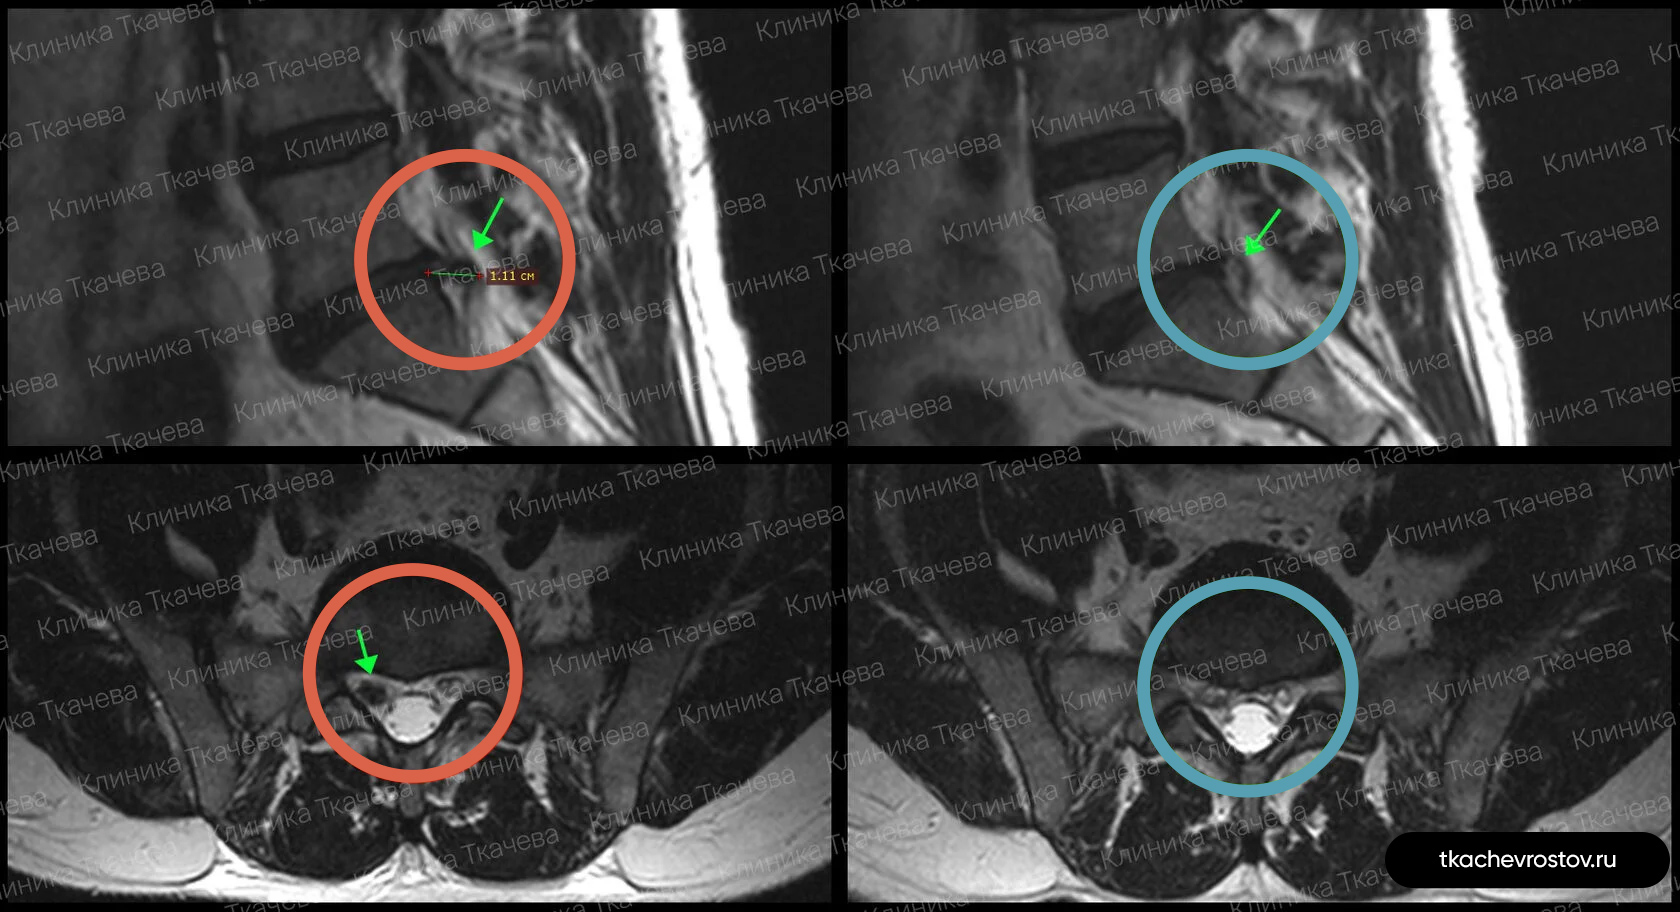

Результаты МРТ до и после лечения

Эти МРТ-снимки представляют собой результаты лечения пациентов в нашей клинике. На них видно полное или частичное уменьшение размеров грыжи.

Грыжа в поясничном отделе L4-L5

Мужчина. Межпозвонковая грыжа в сегменте L4-L5 1.5 х 1.7 см с абсолютным стенозом позвоночного канала. Никакое лечение не помогло, отправили вначале к психиатру, а потом к нейрохирургу.

ДО:

- Интенсивная боль в пояснице, с эпизодическими прострелами

- Ограничение движений в пояснице

- Нарушения сна

- Снижение бытовой и социальной активности

ПОСЛЕ 1 курса:

✓ Наступила частичная резорбция грыжи

✓ Наступило улучшения общего состояния.

ПОСЛЕ 2 курса:

✓ Наступила полная резорбция грыжи

✓ Небольшое восстановление высоты межпозвонкового диска (регенерация пульпозного ядра)

Лечение грыжи заняло 8 месяцев. Было проведено 2 курса лечения по 12 дней.